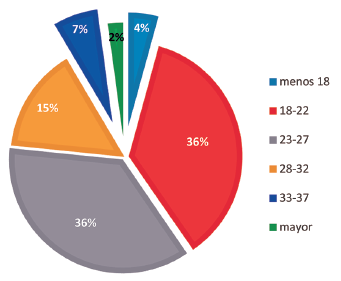

Ricardo Javier Mejía Martínez

|

|

|